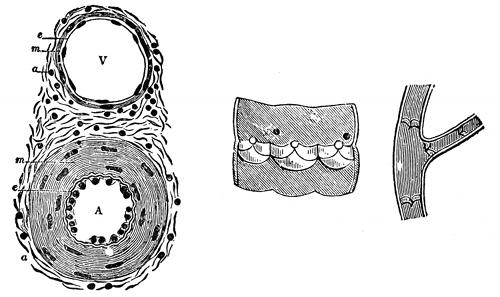

Fig. 2—A cross section of

the skin. (Gray)

Fig. 5—Cross section of

bone. (Sharpey)

If a cross section is made of any

long bone, such as the humerus,

and this section placed under the

low power of the microscope, the

Haversian canal system can be

discerned. The Haversian canal

system consists of the numerous

small openings or canals through

which the blood vessels ramify in

distributing the nourishment to

the bone. Around each individual

canal are seen smaller spaces arranged

in a circle. These are known

as the lacunae (small lakes). Going from the lacunae

are smaller canals which take on the name canaliculae,

and joining all the lacunae together, making the appearance

of concentric circles, we have the lamellae. The

outside covering of the bone is called the periosteum and

the inside covering is called the endosteum. Most of

the long bones and many of the smaller bones are supplied

by a nutrient artery, which enters the bone near

its center, enters the bone marrow, and divides into

two branches, one going up and the other down in the

marrow. The blood is then distributed through the Haversian

canal system. Veins emerge from the long bones

in three places: 1. One or two large veins accompany

[51]

the nutrient artery. 2. Numerous veins emerge from

the articular extremities. 3. Many small veins arise

in and emerge from the compact substance.